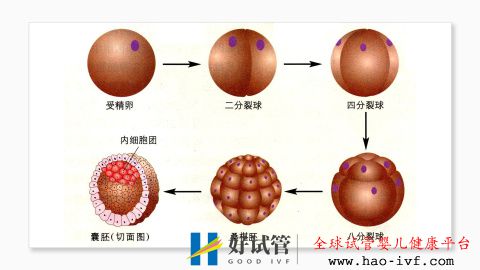

试管婴儿费用大约多少2021年:国内试管之(5)体外受精

这块是医院实验室医生的常规操作,没什么需要我们患者注意的地方,此处不做赘述。

试管婴儿费用大约多少2021年——3.国内一二代试管婴儿费用详解试管婴儿费用大约多少2021年:国内试管之(6)胚胎移植

胚胎移植是将受精卵子移植到子宫内的过程,一般在取卵后第4天,整个过程其实没什么感觉,但移植后,要尽可能地平躺48小时以上,除了必要的上厕所外,基本都躺在床上。有些患者比较谨慎,躺在床上超过72小时都有。